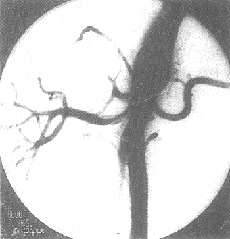

(4)腎動脈栓塞或血栓形成。

5、腎血管性疾患如腎動脈栓塞和血栓形成,腹主動脈瘤,腎靜脈血栓形成等。